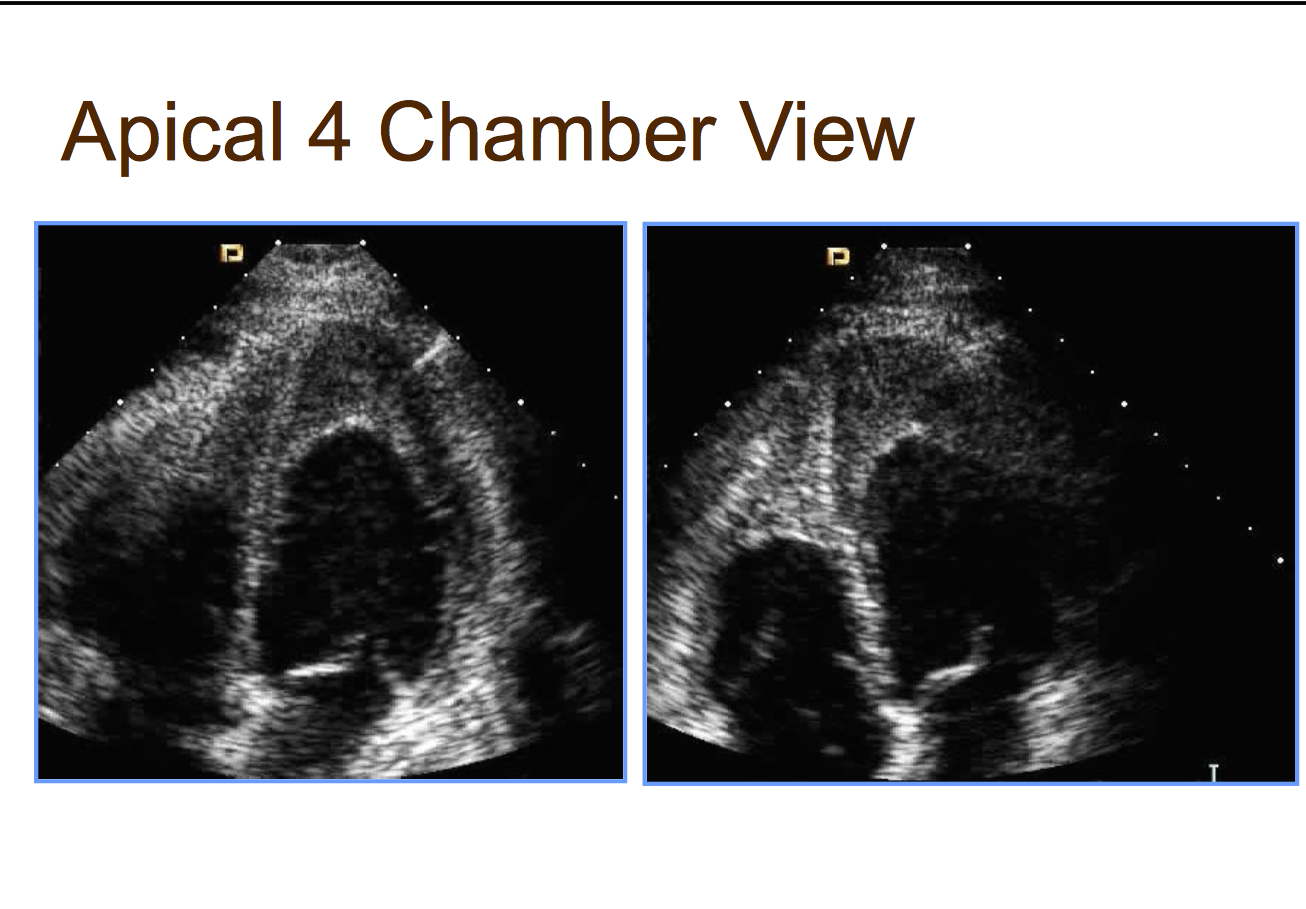

27 F in CHF. Diagnosis?

eosinophilic endomyocardial dz. contrast to look for LV apical thrombis. MV posterior leaflet covered with gook.